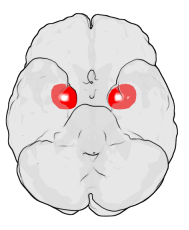

정신질환에서의 편도체 이상

우울증, PTSD, 공황장애 등 다양한 정신질환에서 편도체 기능 이상이 발견됩니다. Rauch et al.(2000)의 연구는 PTSD 환자가 외상과 관련된 자극을 볼 때 편도체 과활성을 보인다고 보고했습니다. 반대로 사회적 무감각이나 자폐 스펙트럼 장애(ASD)에서는 편도체 반응이 감소하는 경향이 있습니다(Baron-Cohen et al., 2000). 즉, 편도체는 과도하거나 부족한 활성 모두가 문제를 일으킬 수 있으며, 균형이 중요한 감정 조절의 허브라고 할 수 있습니다.